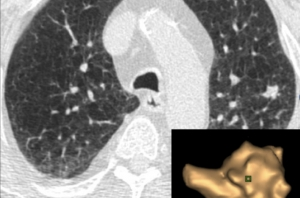

Клиниката по Образна диагностика на МБАЛ „Токуда Болница София” разполага с възможност за полуавтоматизирана оценка на белодробни огнищни лезии, базирана на съвременен софтуерен продукт, обработващ образи от компютъртомографските изследвания. Тази оценка е неразделна част от Протокола за ранно откриване на рак на белия дроб при рискови контингенти с помощта на нискодозова компютърна томография, както и при проследяване на поведението на случайно установени малки огнищни сенки в белодробния паренхим при изследвания, проведени по друг повод.